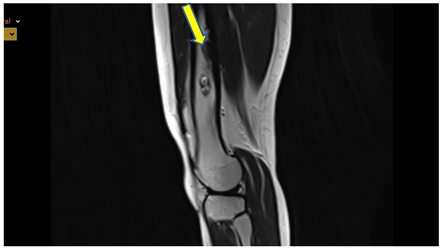

MRI: T2 weighted image, sagittal - sharply demarcated lesion with sclerotic border, high signal intensity in T2 i PD, low in T1, thickened cortical bone, without agressive periostea reaction

See Figure 4. and 5.

PD weighted image, axial and sagittal - sharply demarcated lesion with sclerotic border, high signal intensity in T2 i PD, low in T1, thickened cortical bone, without agressive periosteal reaction.

Given the prolonged interval since her last imaging evaluation, modern radiologic investigations were conducted. MRI and CT showed no abnormalities in the knee's soft tissues, but did reveal focal grade 2 patellar chondromalacia and minimal effusion in the suprapatellar recess. Importantly, four distinct lesions were identified in the left femoral diaphysis: three sharply demarcated round lesions (7-9 mm), and one subcortical lesion with sclerotic margins and imaging characteristics (low T1 signal, mixed T2 and PD signal with chondroid/fibrous components) consistent with residual CMF.

These lesions showed no signs of biological activity and were considered residual findings from childhood CMF. A follow-up MRI in three months was recommended to monitor potential changes.

This distinction is clinically significant. The lesions identified on MRI and CT were small, sharply demarcated, subcortical in location, and surrounded by sclerotic margins, without signs of cortical breakthrough or soft tissue invasion. Their imaging characteristics-low signal on T1 and mixed or intermediate signal on T2 and PD sequences-are consistent with CMF. Importantly, there was no peri-lesional edema or enhancement to suggest active inflammation or growth. Given the patient’s long symptom-free interval and excellent functional status, the current findings are most consistent with residual, inactive lesions rather than true recurrence. To further assess the metabolic activity of the lesions, a low density PET/CT scan was performed. The results showed no significant fluorodeoxyglucose (FDG) uptake in the femoral lesions, which strongly supports the interpretation that these are quiescent residuals rather than active or recurrent tumor tissue. Although CMF is typically a tumor of low metabolic activity, PET/CT can serve as a useful adjunct in ambiguous cases-especially when MRI findings are indeterminate or when clinical suspicion persists. The absence of FDG activity in this case provided additional reassurance and justified a conservative management approach with short-interval follow-up imaging. This case illustrates that not all post-treatment CMF lesions require excision, especially when they remain asymptomatic and radiologically stable. The patient’s current symptoms were unrelated to tumor recurrence and were instead due to pes anserinus bursitis—confirmed by clinical improvement following targeted corticosteroid injection. To our knowledge, only two cases of CMF have been reported in Croatia to date, both involving atypical locations-the mandible and the second metacarpal bone [